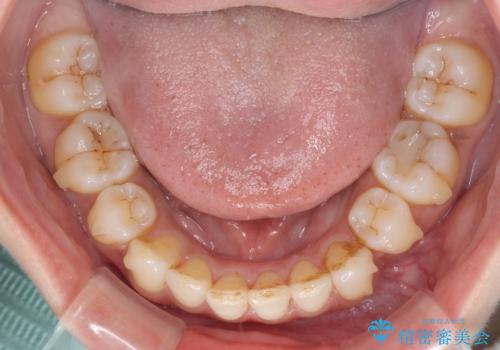

- 上下前歯の叢生を気にして来院された患者様です。

費用を抑え、期間もあまりかけずに治療をしたいとのことで、インビザライン・ライトを用いて矯正治療を行うこととしました。